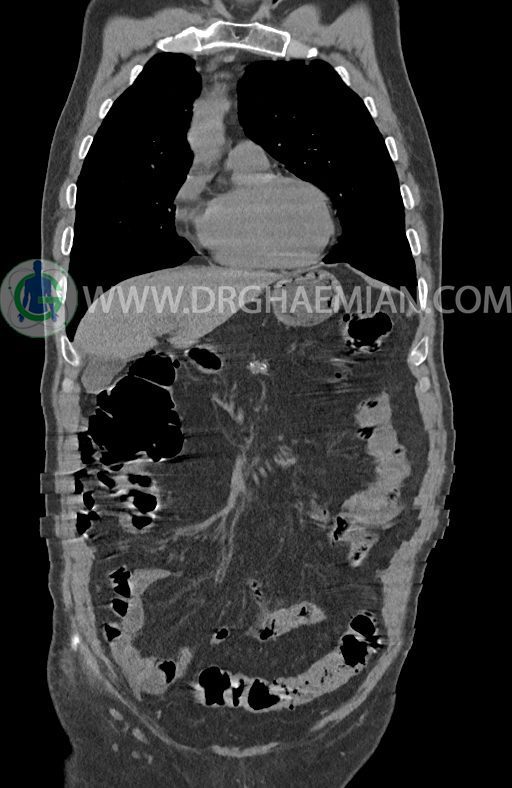

در سی تی اسکن اسپیرال ریه ها و مدیاستن، شکم و لگن با و بدون کنتراست وریدی (مولتی دیدکتور 16 با مقاطع ظریف و بازسازی کرونال) :

پلورال افیوژن، جابجایی محتویات مدیاستن، کلسیفیکاسیون، کیست، فیبروز ریوی و Collection مشهود نیست.

حجم ریه ها، طرح برونکو واسکولر ریه ها، فیشر ها و هیلوم دو طرف طبیعی است.

–افزایش ضخامت تومورال دیستال مری و GEJ در سگمانی به طول 4cm-5cm (T2 or T3)